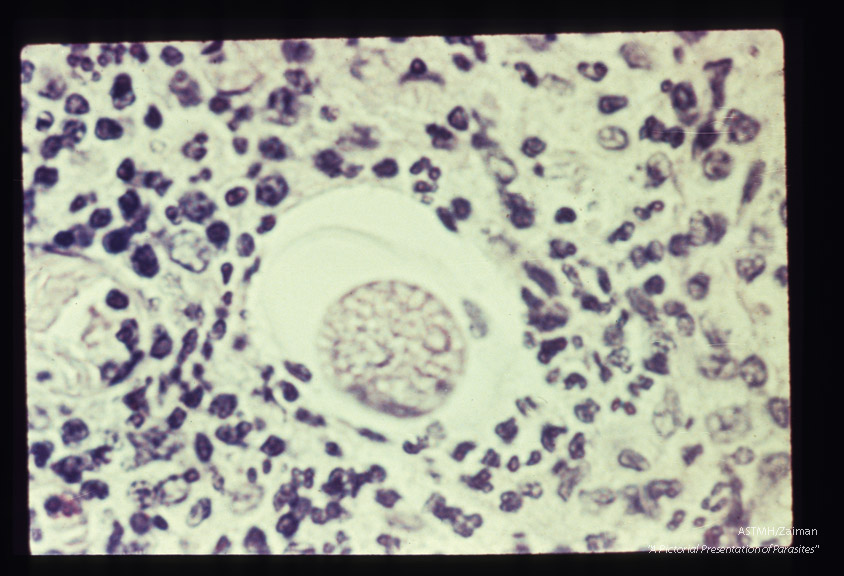

Eggs in peritoneum. The egg shell, without the mamillated coat, can be seen.

Description: Eggs in peritoneum. The egg shell, without the mamillated coat, can be seen.